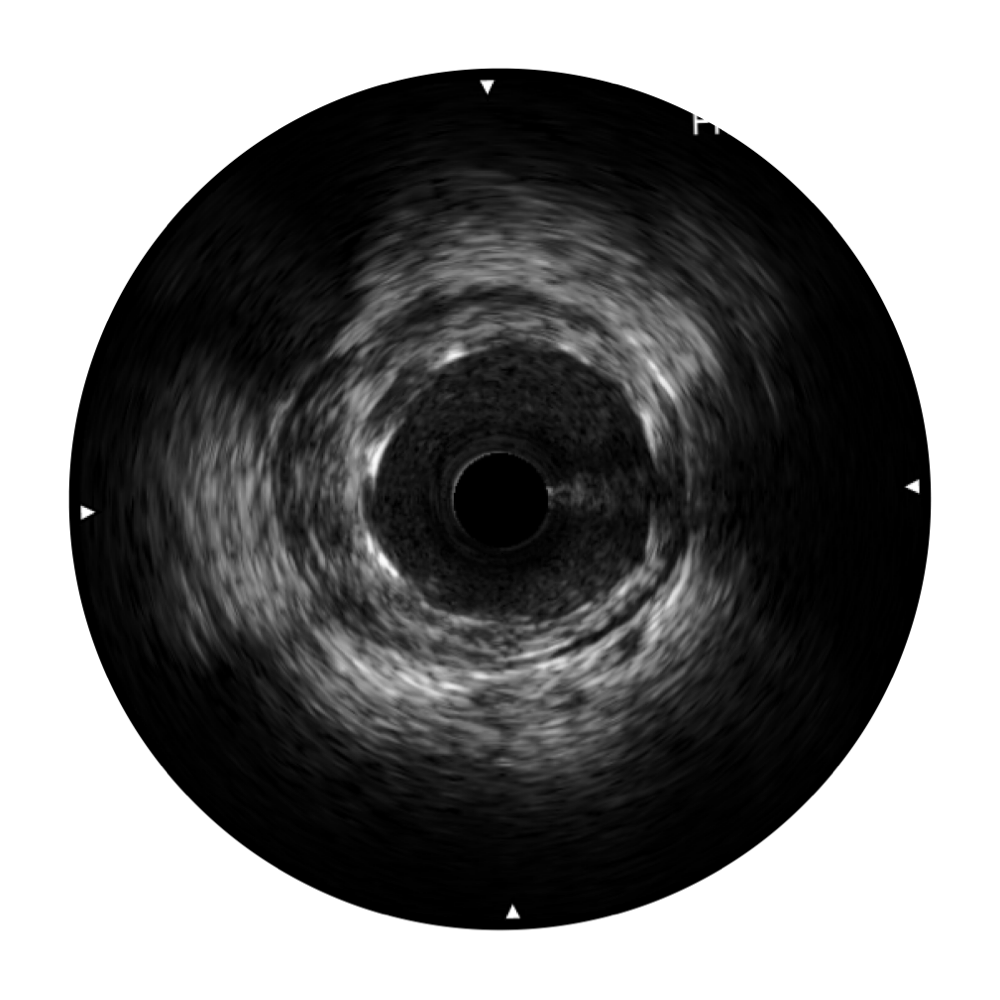

血管内超声(IVUS) 通过对病变程度、性质和累及范围的精确判断,可帮助选择治疗策略和方法,指导介入治疗过程,能够降低主要不良心血管事件,改善预后,在复杂病变介入治疗中用于指导支架置入的优势更为明显。血管内超声(IVUS)已成为精准心血管介入治疗的“金标准”。

哈哈体育官网超宽频成像技术覆盖20-80MHz1或20-90MHz2频率范围, 提供优异的分辨力同时也保证充足的穿透深度

对比传统IVUS导管成像,哈哈体育官网宽频IVUS图像的近场支架梁显影更细腻,远场中膜外血管仍清晰可辨,兼顾远中近,兼顾分辨力与穿透深度